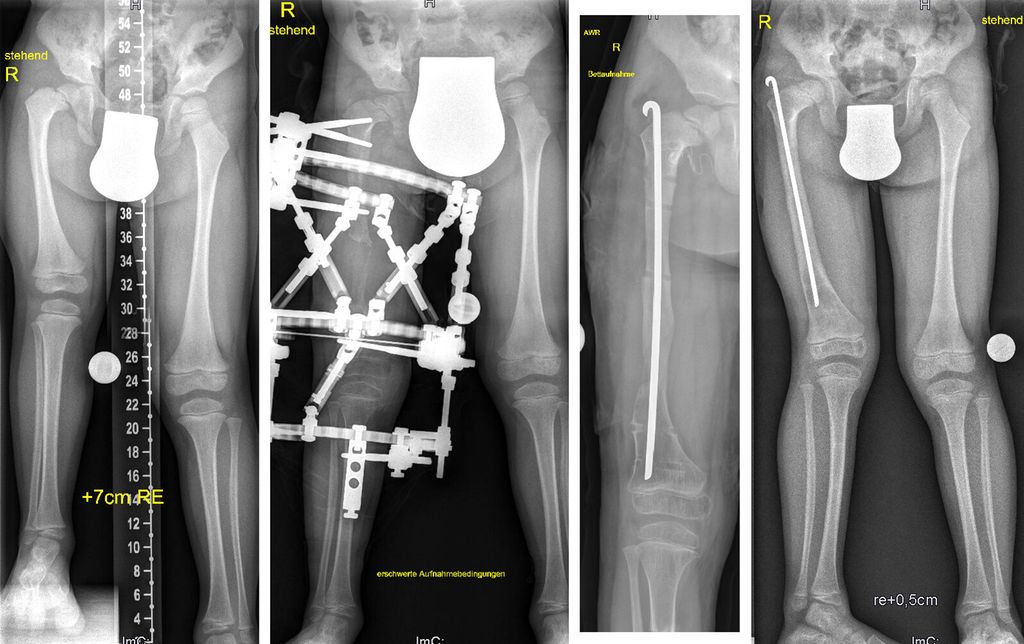

Auch an unserer Abteilung kommt der Hexapoden-Fixateur bei Patienten von 2 bis 92 Jahren zum Einsatz. Hauptindikation an unserer Abteilung sind Achskorrektur und Beinverlängerung im Kindes- und Jugendalter, wobei hier vor allem kongenitale Deformitäten (kongenitaler Femurdefekt, Fibulahemimelie, Tibiahemimelie, posteromediales Bowing) (Abb. 3), posttraumatische Deformitäten und Deformitäten im Rahmen von Syndromen oder metabolischen Erkrankungen (XLH) behandelt werden.

Abb. 3: Bei diesem 4-jährigen Patienten mit kongenitalem Femurdefekt (CFD) erfolgten eine Verlängerung und Achskorrektur am distalen Femur mittels TSF. Zusätzlich wurden die Retrotorsion am proximalen Femur und ein Teil der Varusfehlstellung akut korrigiert. Der Knieüberbau verhindert bei instabilem Kniegelenk bei angeborener Kreuzbandaplasie/Hypoplasie eine Subluxation des Gelenks. Das Knie wird in der Nacht in Streckung fixiert, um eine Kontraktur bei Verlängerung zu verhindern, welche in diesem Fall knapp über 5cm betrug. Um eine Fraktur des unreifen Kallus, wie sie bei CFD häufig ist, zu verhindern, erfolgte simultan mit dem Apparatabbau eine Fixierung mit Rush-Pin. Dieser wurde 9 Monate später nach Röntgenkontrolle wieder entfernt. Der rezidivierende Valgus, der bei CFD typisch ist, kann zwischen den Verlängerungsschritten mittels Wachstumslenkung einfach korrigiert werden